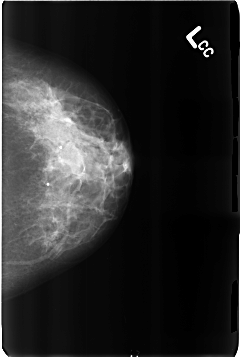

B_3169_1.LEFT_CC

LEFT_CC LINES 4632 PIXELS_PER_LINE 3112 BITS_PER_PIXEL 12 RESOLUTION 50 NON_OVERLAY